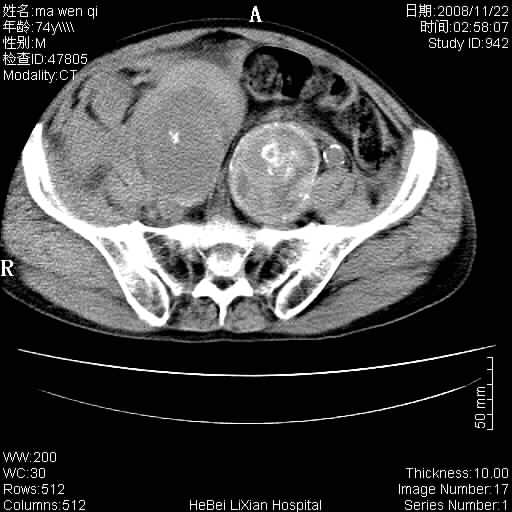

患者男 74岁.突然昏迷,休克6小时.血压70/30,头颅ct未见异常,既往体健.

补充病史,保留导尿10小时,尿袋内只有少许尿液,患者于住院后15小时后去世.

腹主动脉、双侧髂动脉夹层动脉瘤破裂出血进入腹腔。

考虑双侧髂a瘤,伴破裂出血

1)考虑双侧髂动脉瘤并右侧动脉瘤破裂出血,右侧腹膜后及腹腔积血。2)双侧腹股沟疝。

1)考虑,腹主动脉、双侧髂动脉夹层动脉瘤破裂伴右侧腹膜后及腹腔积血。2)双侧腹股沟疝。

1)考虑胸、腹主动脉、双侧髂动脉瘤并右侧动脉瘤破裂出血,右侧腹膜后及腹腔积血。2)双侧腹股沟疝。